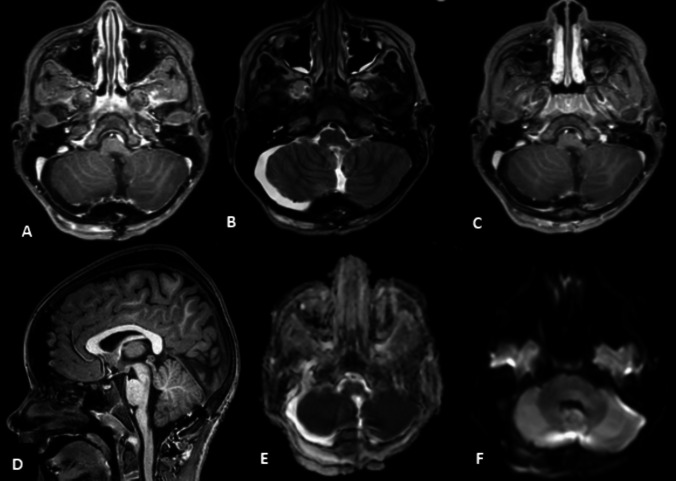

A 7-year-old boy presented to the hospital with recurrent nausea and vomiting over 2 weeks. A cranial MRI revealed a large heterogeneous lesion in the posterior fossa extending from the fourth ventricle to the foramen magnum with contact to the brainstem. The lesion showed moderate diffusion restriction and multiple small cystic components. The child underwent gross total resection. The primary histological findings suggested proliferative active tumor without further definition. The extended histological examination 3 weeks later confirmed the diagnosis of astroblastoma. Due to complete resection and full recovery of the patient, watchful waiting with radiological follow-up was recommended. Astroblastoma is an extremely rare tumor especially in the posterior fossa. However, it should be considered as a differential diagnosis in every tumor presenting the discussed radiological and histological features, especially in young aged patients.